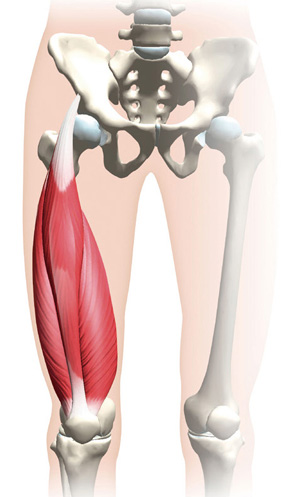

最新デザインの 膝関節の難治性病態に対する手術―日常診療で困ったときのこの一 医学一般